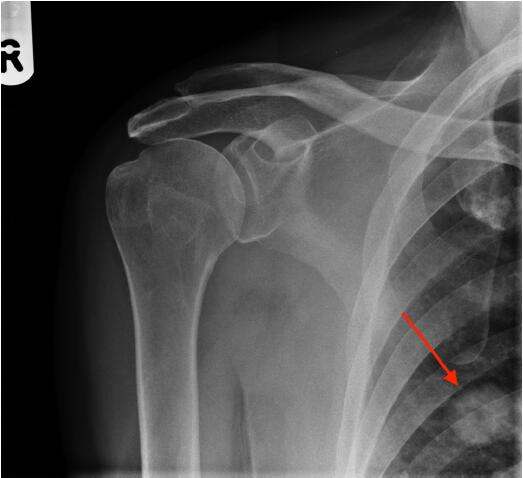

圖2肩X光片顯示一空洞性肺結(jié)節(jié),約2cm。很可能是原發(fā)性肺癌,需要轉(zhuǎn)診至肺癌多學(xué)科小組。

圖2右肩前位X光平片,紅色箭頭指示一空洞性肺結(jié)節(jié)

該例患者接受了胸部和腹部CT掃描,隨后取了活檢,證實(shí)為T2N0M0原發(fā)性肺腺癌。對(duì)給患者予以手術(shù)切除,2年隨訪時(shí)仍無病。